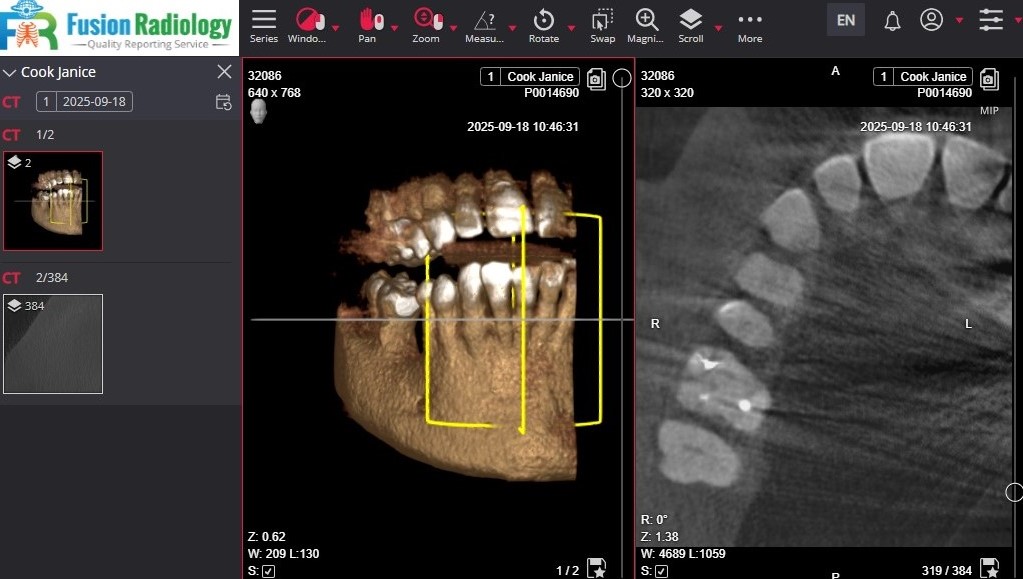

Seamless CBCT Scan & Reporting – All in One Platform

Here at Fusion Radiology, we have designed and implemented a fully integrated all in one system for the exchange of scans and reporting with dental practices and ensuring a smooth operation and ensuring ease of use of the system. -